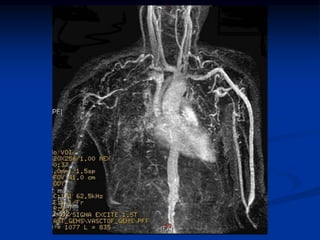

ARTERITIS DE TAKAYASU

• Vasculitis granulomatosa de arterias de mediano

y gran calibre

• Engrosamiento irregular de las paredes de la

aorta y sus ramas con arrugamiento de la intima.

• Se desconocen la causa y la patogenia aunque se

sospecha de mecanismos autoinmunes.

• Puede ocurrir insuficiencia valvular aortica por

dilatación de la raíz de la aorta.